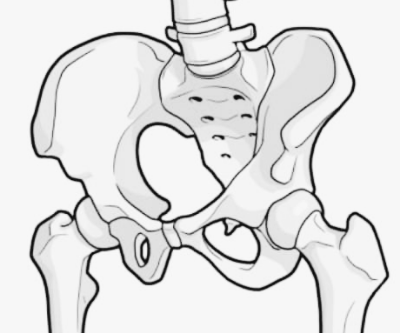

엉치뼈가 아픈이유 통증 원인 엉치뼈 통증이란? 위치와 증상부터 파악하자

엉치뼈는 해부학적으로 천골과 미추(꼬리뼈)로 구성된 부위입니다. 이 부위에 통증이 생기면 다음과 같은 증상이 나타날 수 있습니다.